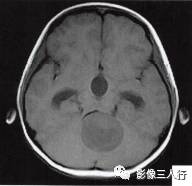

(二)影像所见

头颅MRI扫描示:小脑上蚓部见团块状异常信号影,边缘清楚,大小约4.5cm×3.5cm×3.7cm,T1WI(图B)等信号,中心可见更低信号,T2WI(图A)呈髙信号,水抑制(图C) 等信号,中心呈更低信号,周边可见轻度高信号水肿区。增强后(图D〜F)病灶可见明显环形强化,壁较厚,内壁欠光滑,邻近小脑及第四脑室受压,第三脑室、双侧脑室扩张积水。

诊断:小脑上蚓部占位,考虑肿瘤性病变,以毛细胞型星形细胞瘤可能性大。